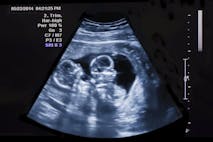

Vermont’s extreme abortion law prevents justice for preborn twins killed